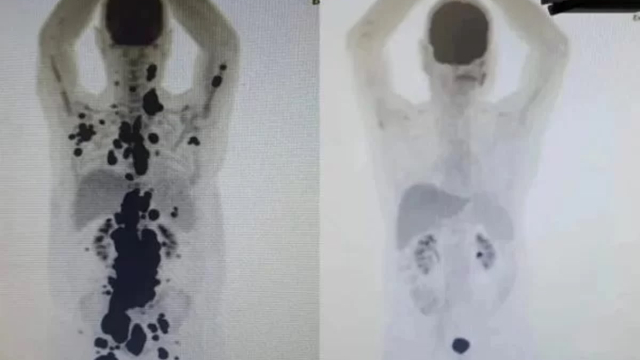

No Brasil, está sendo realizado um estudo com terapia celular CAR-T, voltado para o tratamento do câncer. Um dos participantes desse estudo é um paciente diagnosticado há 13 anos, que apresentou remissão completa dos tumores em apenas um mês. Esse paciente é um dos 14 indivíduos acompanhados na rede pública de saúde que estão participando desses estudos com a terapia CAR-T.

Paulo Peregrino, de 61 anos, lutava contra um linfoma há cinco anos, além de ter enfrentado outros tumores nos últimos 13 anos. O câncer estava em um estágio tão avançado que ele estava próximo de ser encaminhado para cuidados paliativos. No entanto, Paulo foi selecionado para participar de um teste com uma nova técnica, oferecendo-lhe uma chance de esperança e tratamento.

A terapia celular CAR-T é considerada um dos avanços mais promissores na luta contra o câncer. Essa abordagem revolucionária envolve a modificação das células de defesa do próprio paciente em laboratório, permitindo que elas sejam capacitadas a reconhecer e destruir as células cancerígenas. Após esse processo de modificação, as células são reintroduzidas no organismo, onde se multiplicam e reforçam a resposta natural do corpo contra o tumor.

Essa técnica tem se mostrado particularmente eficaz no tratamento de cânceres sanguíneos. No Brasil, os estudos estão focados na aplicação da terapia CAR-T para combater a leucemia linfoblástica B e o linfoma não-Hodgkin de células B. Essas pesquisas representam uma esperança para pacientes que sofrem dessas condições, oferecendo novas possibilidades de tratamento e potencialmente melhorando os resultados clínicos.